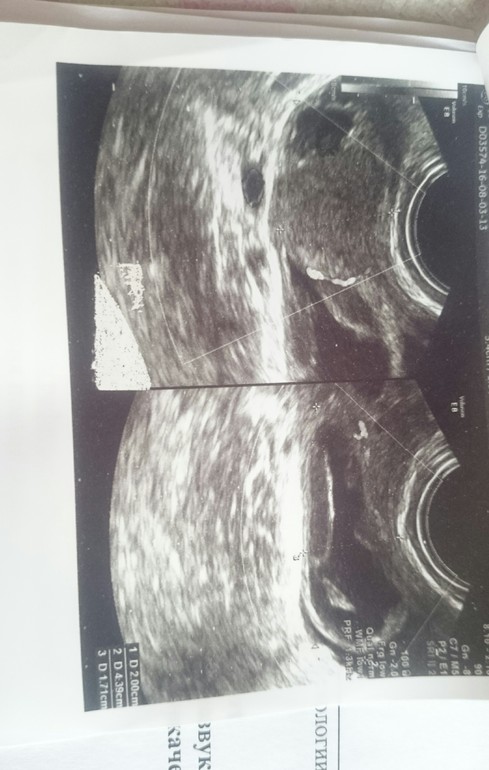

Цикл у меня 28-34. Недавно впервые в жизни на 18 д.ц. пошла кровь. Сходила на узи. Вот результат. Узист толком как всегда ничего не объяснил. Сказал - воспаление у тебя. Но недавно сдавала мазок,всё было идеально(( Девочки, всё совсем у меня плохо? Смогу ли я вообще когда-нибудь забеременеть? Разъясните,пожалуйста. Очень буду ждать ваших ответов. Сижу плачу..

Это почти то, о чем я в комментариях вам писала в предыдущем посте. Хронический двусторонний аднексит - воспаление обоих маточных труб. Вам к врачу надо, лечить срочно.

Эндометрит нужно лечить,конечно. Сдайте посев с чувствительностью к антибиотикам. Хронически эндометрит лечится сначала антибиотиками, потом физиотерапией и витаминотерапией. Про кисту не поняла, она у вас первый раз на узи или давно? Может это фолликулярная киста, она сама уйдет через 1-3 цикла. Жёлтое тело есть, значит О была. Вылечите воспаление и сможете забеременеть, конечно. Не надо плакать, все будет хорошо)

Врач описывает признаки хронического воспаления. В данный момент едва ли можно говорить об обострении, так как протекает оно с лихорадкой и изменением анализа крови, который Вам стоит сдать. По поводу яичников - не совсем поняла, почему не вынесли в заключение жидкостное образование, описанное в протоколе. Кровь , вероятнее всего, была в момент овуляции. Это вариант нормы, если эпизод был однократный и не длительный. Сейчас вам лучше заняться решением вопроса о дообследовании эндометрия.